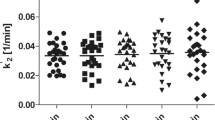

Use of venous input function

Equilibrium was not reached between arterial and venous blood data measured at four timepoints. At 30 min, arterial blood samples showed higher plasma concentrations than venous blood samples, with an average arterial-venous difference of 14.3 ± 12.2% (range 7.3 to 32.5%). Plasma concentrations were almost equal at 60 min, with an average difference of − 1.5 ± 5.9% (range − 8.0 to 0.0%) between arterial and venous blood data; however, at later timepoints, the average difference became greater (− 5.5 ± 14.0% (range − 13.5 to 15.4%) at 120 min and − 25.0 ± 21.0% (range − 54.7 to − 6.7%) at 180 min (Fig. 2).